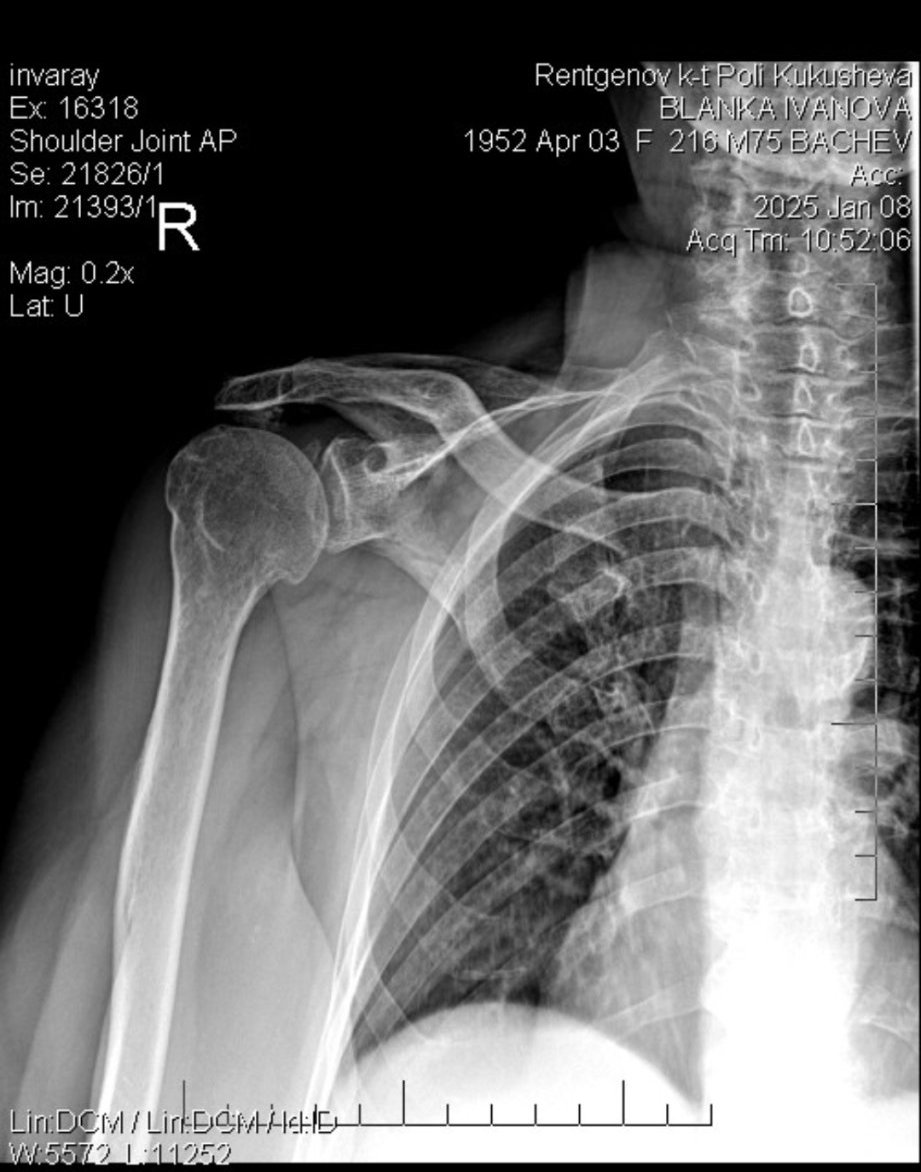

Здравейте д-р. Росен Георгиев!

От няколко месеца баба ми има болки в ръката, най-вече в лакътя.

Ходихме на лекар на 23.12.2024 година ,който я изпрати на снимка,на която излезе,че има остеопороза на рамото и бурсит на лакътя....

Началото на януари отидохме отново на преглед при същия доктор и й изписа  лекарства,от които нямаше никакъв  ефект - болката си продължава до ден днешен.....

Какво може да се направи в такъв случай Sad?

Здравейте, благодаря за въпроса.

Остеопорозата е заболяване, което протича безсимптомно. Първите ѝ симптоми най-често са фрактури.

Често се забелязва на рентгенови снимки, но се доказва чрез остеодензитометрия.

Бурситът е също често срещано състояние, което се повлиява сравнително лесно.

Моля да предоставите както фото снимки на лакътната става, така и рентгенови снимки.

Ето това е снимката,която поискахте

Здравейте,

от рентгенографията се вижда, че имате артрозни промени, от които може да се дължат и Вашите оплаквания.

С уважение:

Д-р Георгиев